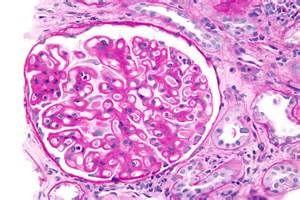

肾内病理图解 | 膜性肾病

肾内病理图解 | 膜性肾病